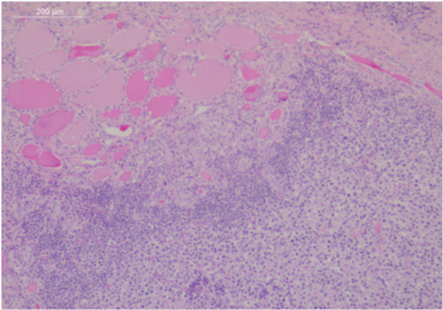

The patient underwent imaging of the neck for further evaluation. CT demonstrated marked enlargement of the thyroid gland, left greater than right. There was mass effect on the trachea, decreased diameter of the trachea and enlarged neck nodes (Figure 1). The patient underwent total thyroidectomy.

Figure 1 Neck and thorax CT scan. The pre-treatment figures show a large mass compressing the trachea extending on the anterior chest wall